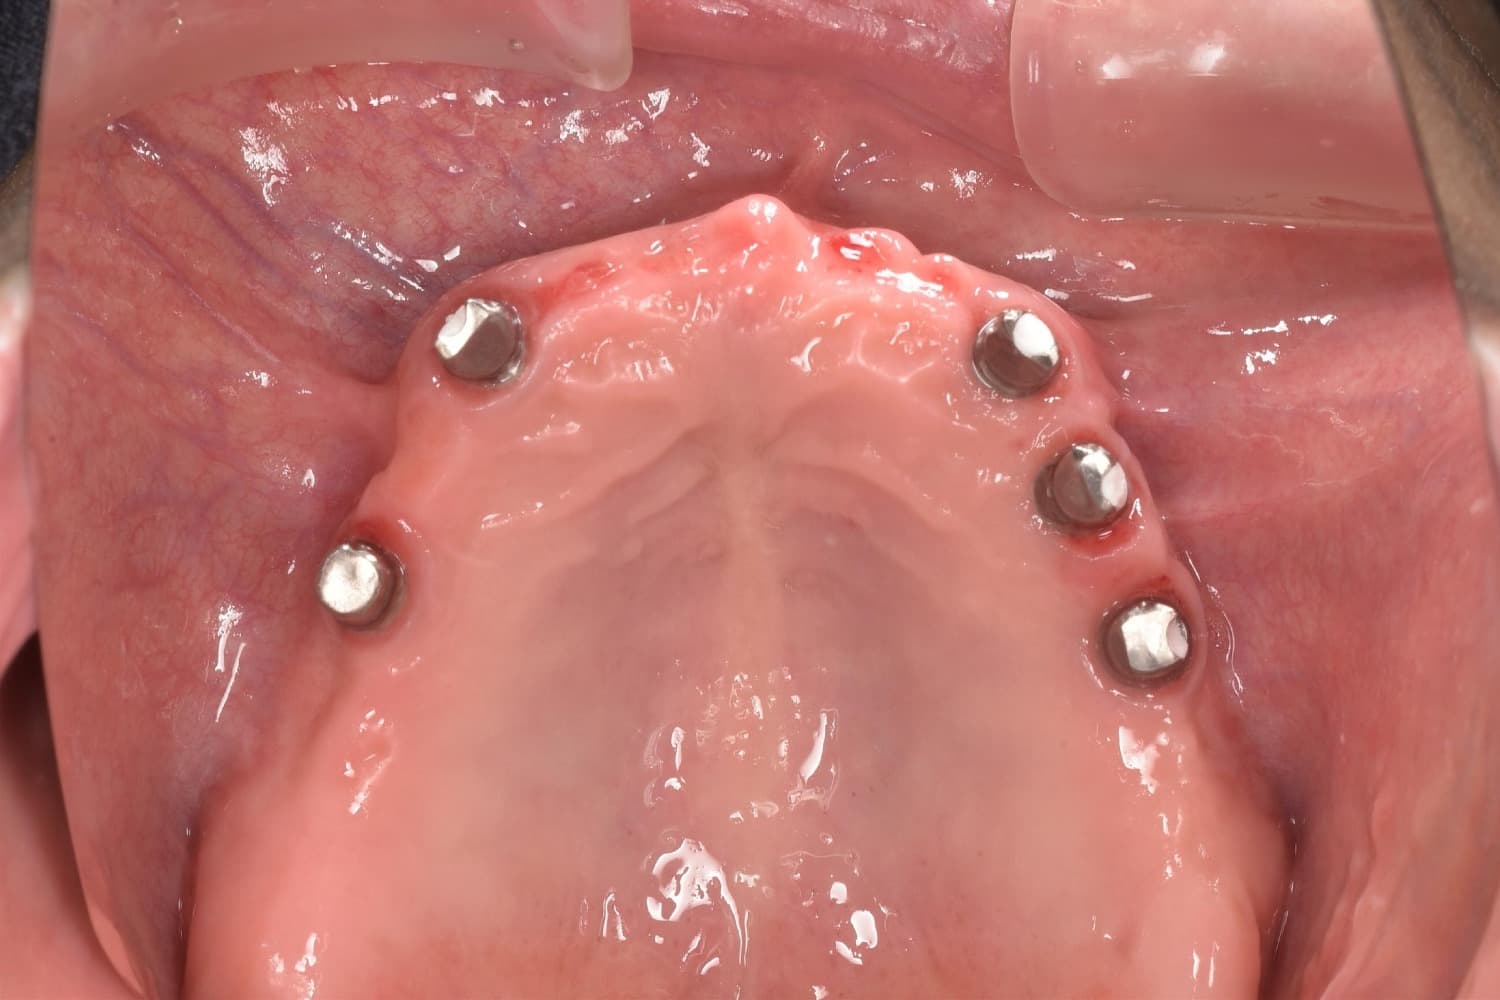

上顎のインプラント治療

Before

After

上顎全ての歯が保存不可能。5本のインプラント埋入を行いました。 費用や清掃性を考慮し、短縮歯列での治療としました。 治療後は見た目も満足され、何でも食べることが出来ると、患者様も非常に喜ばれています。

年齢

60代

性別

女性

主訴

しっかり咬めるようになりたい。見た目も綺麗にしたい。

治療期間

6ヵ月

治療回数

12回

費用

上顎全て:約300万円

副作用・リスク

術後の腫れや痛みの可能性、インプラントの骨結合不良、清掃不良による治癒不全